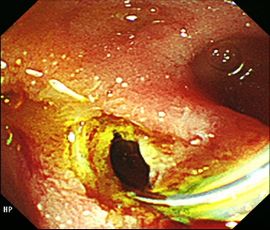

[総胆管結石] 手術:内視鏡的乳頭括約筋切開術:EST

内視鏡画像